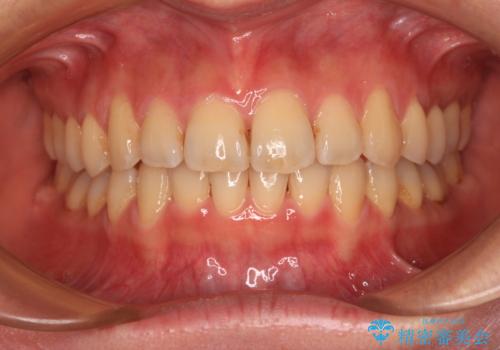

- デコボコと飛び出している前歯を気にして来院された患者様です。

歯列としてはインビザラインでもワイヤー矯正でも対応できるものでしたが、奥歯の咬み合わせを見た時に上顎がやや前方にあり、インビザライン単独では時間のかかってしまう可能性があるため、補助装置を治療当初に使用することで、インビザラインによる治療をスムーズに行えるように計画しました。

インビザラインは得意・不得意の差がはっきりとしているため、補助装置やワイヤー装置などをうまく活用することで、治療期間を短縮するとともに、より理想的な仕上がりを達成することができます。